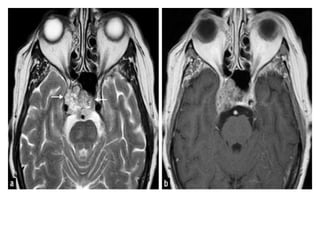

• #20 Carotid-cavernous fistula: axial T2-wi (a) of a carotid-cavernous fistula appearing as a heterogeneous signal with flow voids of the right cavernous sinus (black arrows). Note the dilatation of the superior ophthalmic vein (dotted arrow) and the carotid-cavernous fistula (white arrow) on an arterial TOF of another patient with a carotid-cavernous fistula (b)

• #23 Tolosa Hunt syndrome: axial (a) and coronal (b) T2-wi, sagittal (c) enhanced CT, showing a insular hypointense enlargement of the left cavernous sinus (arrows) with an enhancement and an extension to the orbital apex (star on image c). These findings are consistent with a Tolosa Hunt syndrome.

• #24 Tolosa-Hunt SyndromeT2 iso-hypointense signal in the left cavernous sinus with enhancement Enhancement is also seen in the left superior orbital fissure